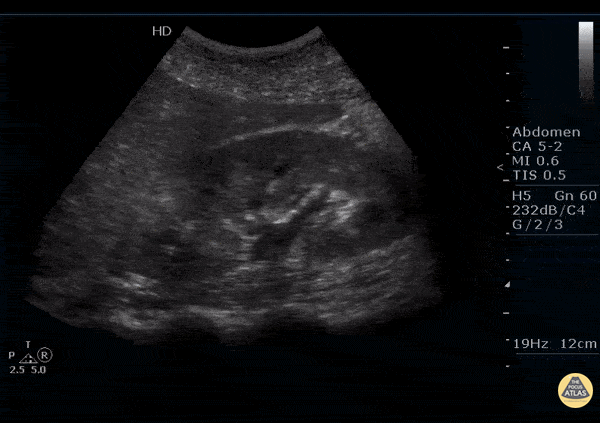

Renal/GU - Acute Focal Nephritis

Right presented with right flank pain. A known ureterovesical junction stone is present. But also notice the focal hyperechoic area at the superior pole of the kidney. This patient was diagnosised with acute focal nephritis. This is on spectrum somewhere between acute pyelonephritis and renal abscess. Image courtesy of Robert Jones DO, FACEP @RJonesSonoEM Director, Emergency Ultrasound; MetroHealth Medical Center; Professor, Case Western Reserve Medical School, Cleveland, OH View his original post here